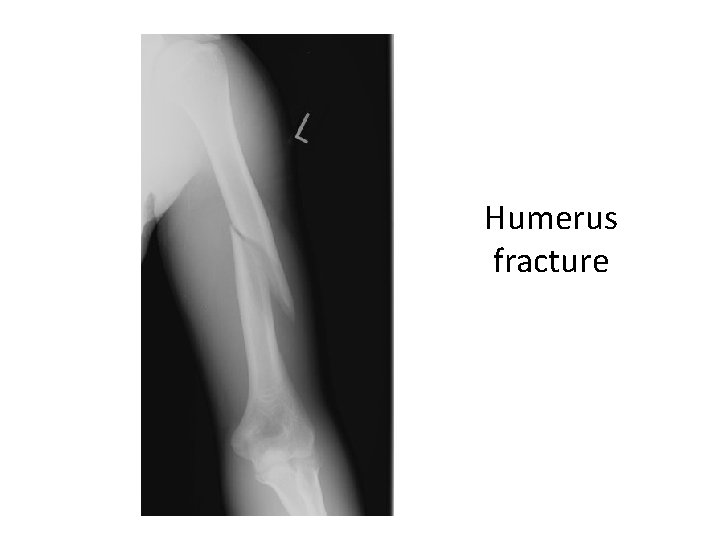

Humerus fracture